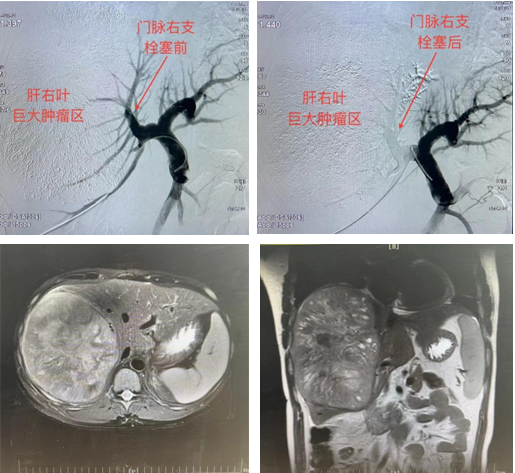

经与患者家属充分沟通、知情告知后,开始实施阶梯式治疗方案。由于前两步治疗的顺利完成,第三步经皮门静脉栓塞术(PVE)也很快实施。PVE术前由超声诊断中心关蕾医师引导,微创介入科颜昭勇医师穿刺门静脉成功,其后微创介入团队先后行门静脉造影、门静脉右支主干及其分支(肿瘤侧)充分栓塞。造影显示肿瘤侧门脉显影消失,提示门脉栓塞成功,手术顺利结束,患者安返病房。